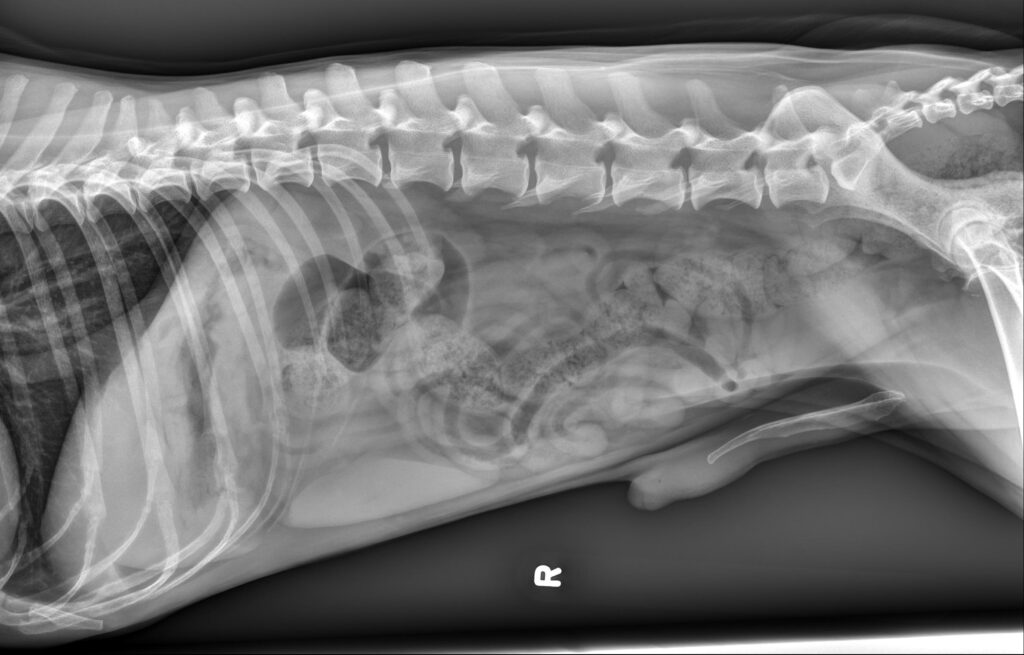

Radiology Quiz September 2025

History 10 year old male castrated dog. History of chronic hematochezia for the last 3 months.